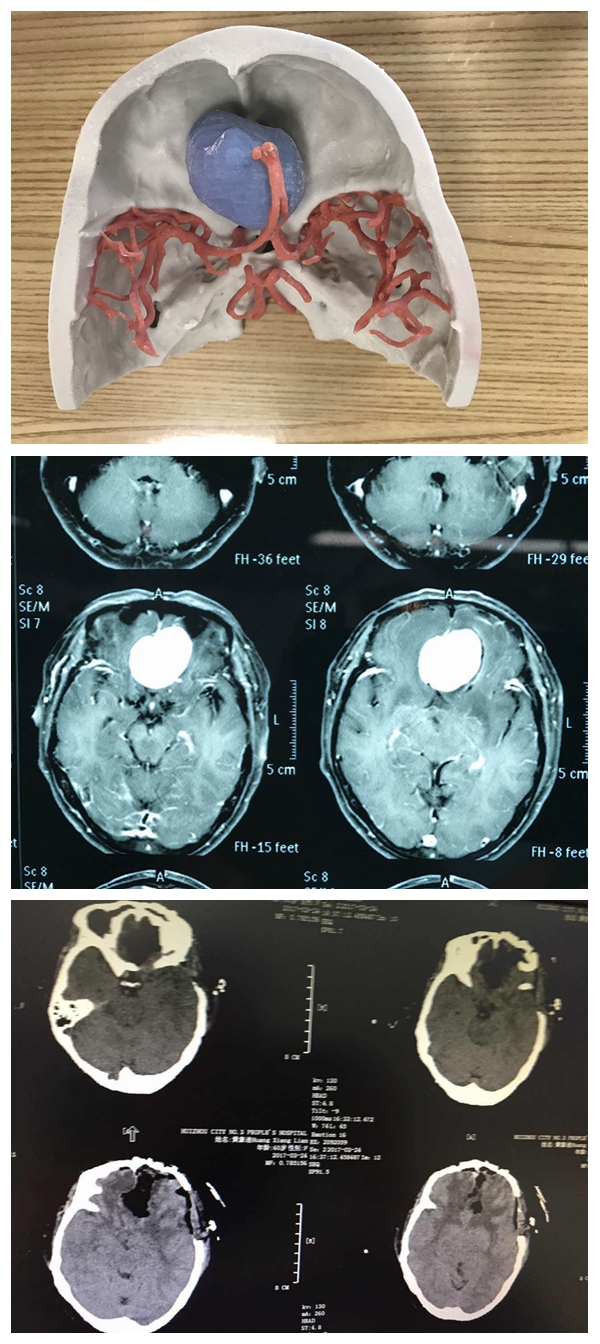

第一例3D模型和術(shù)前術(shù)后CT

據(jù)了解,首例為前顱㡳腫瘤顯微切除手術(shù),患者為老年女性,既往有糖尿病史,經(jīng)多學(xué)科會(huì)診后確定手術(shù)方案。在李雪松主任和科室醫(yī)生的精誠(chéng)協(xié)作下,手術(shù)順利完成,不僅完全切除腫瘤、顱底重建,還完好地保存重要的血管和神經(jīng),避免腦功能受損,極大地提高了患者的生存質(zhì)量。